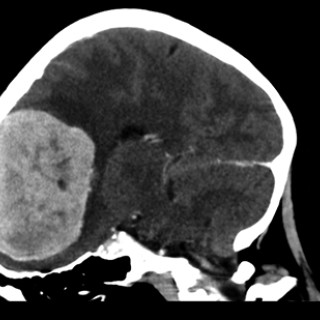

En mann i 20-årene ble innlagt med hodepine, svimmelhet, oppkast, slapphet og vekttap. Cerebral MR-undersøkelse viste diffuse, konfluerende forandringer i hvit substans, forenlig med cerebral vaskulitt. Konvensjonell angiografi med selektiv injeksjon i begge karotider og a. vertebralis høyre side viste normale arterier uten kalibervekslinger eller okklusjoner. Prøver fra spinalvæsken viste økt antall mononukleære celler, overveiende modne lymfocytter, med 107 leukocytter per kubikkmillimeter (≤ 5 leukocytter per mm³) og økt mengde totalprotein 0,94 g/l (0,10 – 0,40 g/l). Øyeundersøkelse viste...